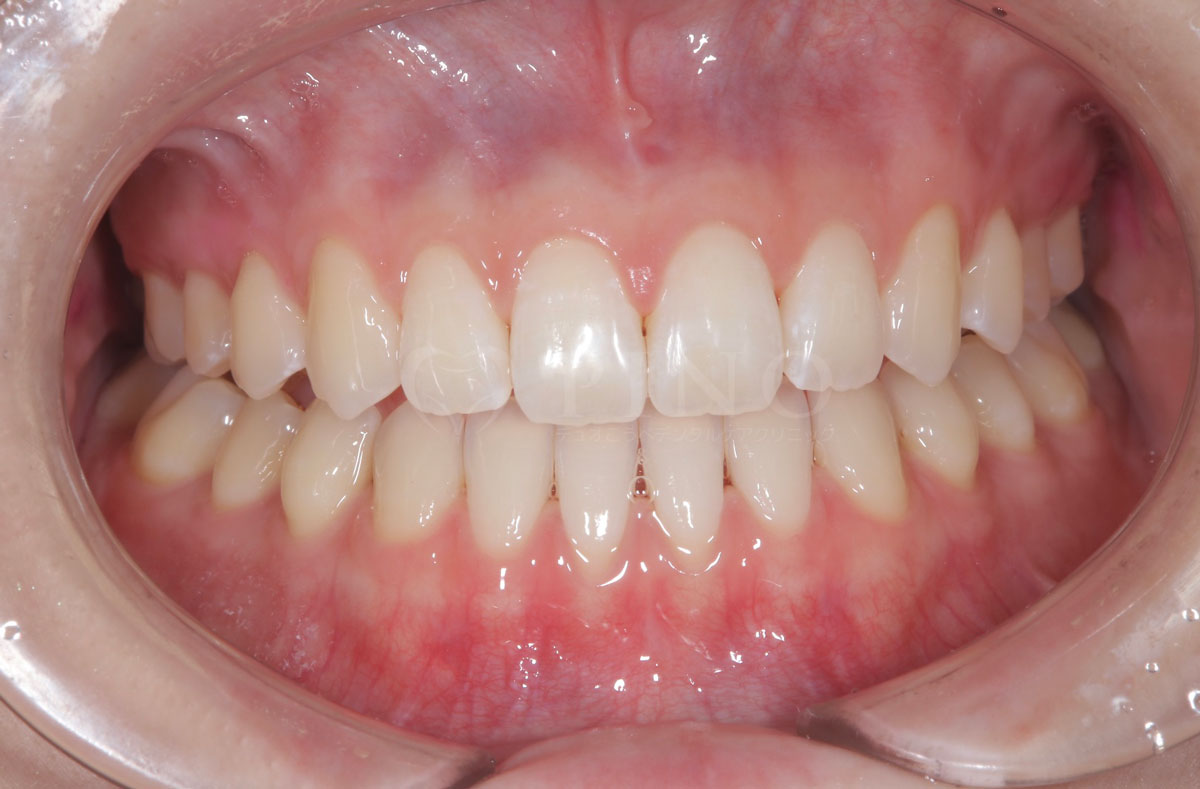

症例8:歯が全体的にガタガタして気になる(30代女性)

主訴 歯が全体的にガタガタして気になる 診断名 上下顎1級叢生 治療方法 マウスピース全顎矯正 抜歯 あり 上2本 オルソパルス あり 治療期間 1年5ヶ月 費用 891,000円+補綴治療費(セラミック320,000円) 副作用・注意点 歯を抜く際に痛みを伴う可能性がある、矯正後後戻りを防ぐためリテーナーの使用が必要となる -